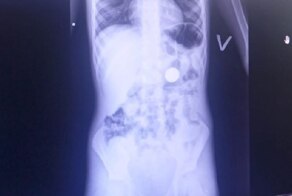

- 6-летний мальчик проглотил монетку ради любопытства